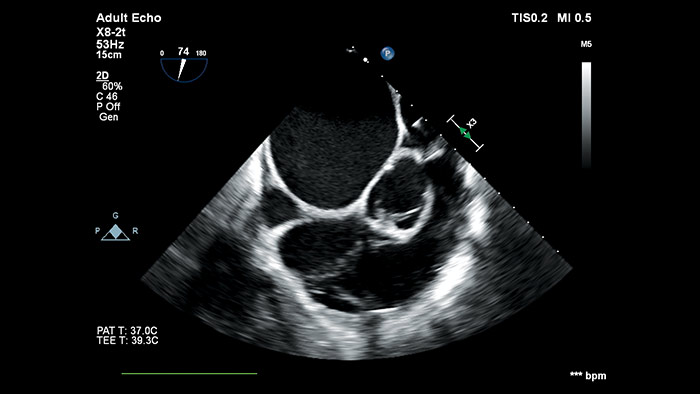

フィリップスのAnatomical Intelligence for Ultrasound(AIUS)は、高度な心臓のモデル化と実績のある定量化機能により、使いやすさ、高い再現性を実現。新しいレベルでの臨床情報の提供を可能にし、現代の医療現場が直面する経済的および臨床的課題に対応します。

AIUSは決まった手順を自動化し、ユーザーによる操作を最小限に抑えてコンピュータ主導解析を行う機能を備えています。臓器の構造を自動で認識し、解析を行うことでスクリーニング診断や計測の質を向上させ、心エコー検査をより迅速に、再現性高く実行することをサポートします。